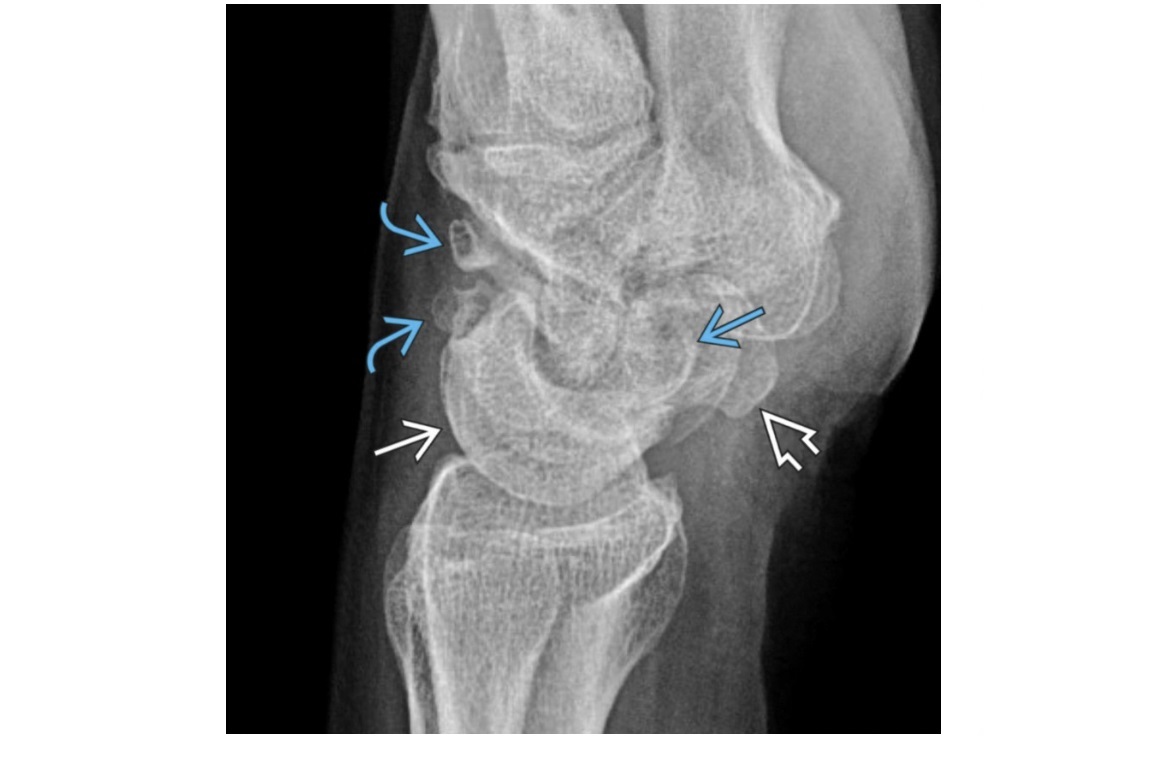

Tillaux fracture

Salter-Harris 3 = through the anterolateral distal tibial epiphysis